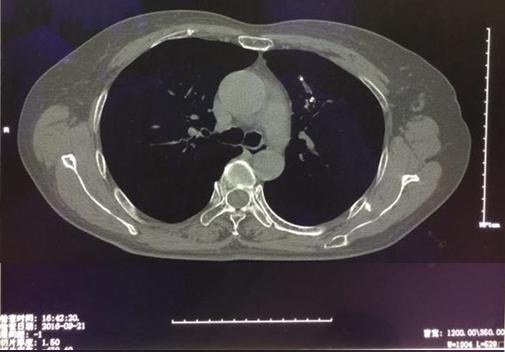

病例1:结核所致右主支气管瘢痕性狭窄

病例2 恶性肿瘤所致气管狭窄

理结果:鳞癌.